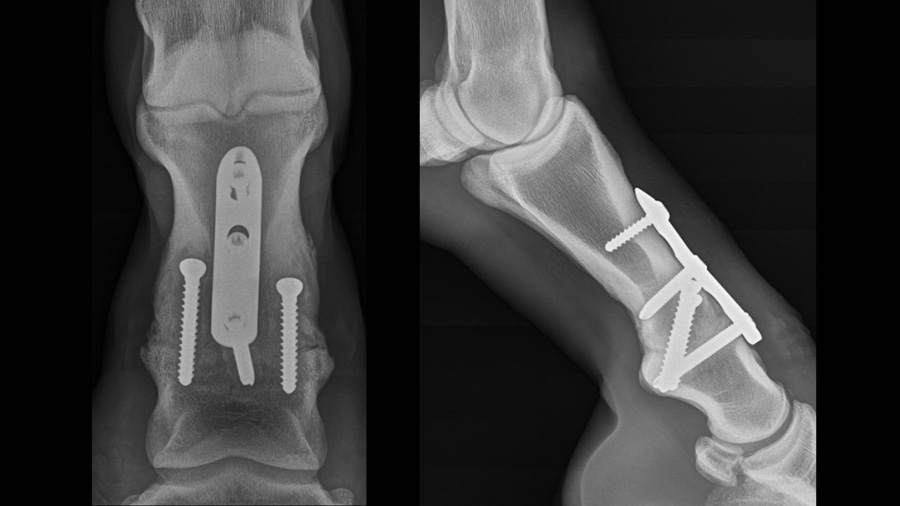

The standard construct for PIP arthrodesis consists of two abaxial, transarticular 5.5mm cortex screws placed in lag fashion with an axially positioned 3-hole PIP-LC plate (Fig. 3).

The stacked combi-hole (H1) is positioned just distal the subchondral plate of the proximal aspect of the middle phalanx with the remaining combi-holes overlying the proximal phalanx, the middle combi-hole (H2) lies adjacent to the joint in the distal aspect of the proximal phalanx, and the most proximal combi-hole (H3) is near the diaphysis of the proximal phalanx. Palmar/plantar transartricular compression is achieved with the transarticular lag screws. Dorsal compression is accomplished by initial placement of a 5.0mm locking screw in H1 followed by the unicortical cortex screw in H3 placed in the load position. When the cortex screw in H3 is fully tightened, dorsal compression is achieved. Angle stable fixation is accomplished by placing a 5.0mm locking screw in H2 of the plate.

Major variations in the above technique include placing the compression generating cortex screw in H2 and using a bicortical locking screw in H3, using a bicortical screw in H3 instead of a unicortical screw, and placing additional transarticular screws abaxially. All of these provide an acceptable construct and meet the criteria for arthrodesis when applied using the standard approach with removal of all accessible articular cartilage. Whether any of the above variations are clinically superior or improve patient outcomes is debatable and will require further investigations documenting results in a large number of patients. The rationale for the construct performed at our hospital is discussed below.